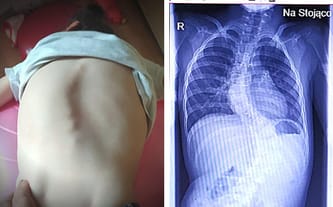

Ubytek przegrody międzykomorowej, wrodzona wada rozwojowa dużych tętnic, zaburzenia funkcji układu krążenia, skolioza kręgosłupa, zespół Williamsa, encefalopatia